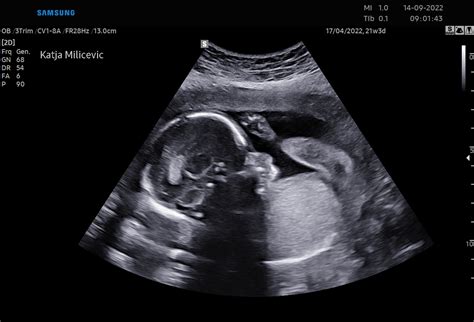

Z ultrazvokom se redno spremlja rast ploda in ocenjuje količina plodovnice. Če zdravniki odkrijejo preveč ali premalo plodovnice, preverijo, če obstaja možen vzrok. Lahko se opravijo krvne preiskave, da bi preverili, ali so prisotne okužbe ali sladkorna bolezen pri materi, ki bi lahko vplivale na količino plodovnice. Ultrazvok in drugi testi, vključno z morebitno amniocentezo, se lahko opravijo za preverjanje prirojenih okvar in genetskih nepravilnosti pri plodu. Plodov srčni utrip se redno spremlja, ko plod leži pri miru in med premikanjem, kar dodatno ocenjuje njegovo dobrobit.